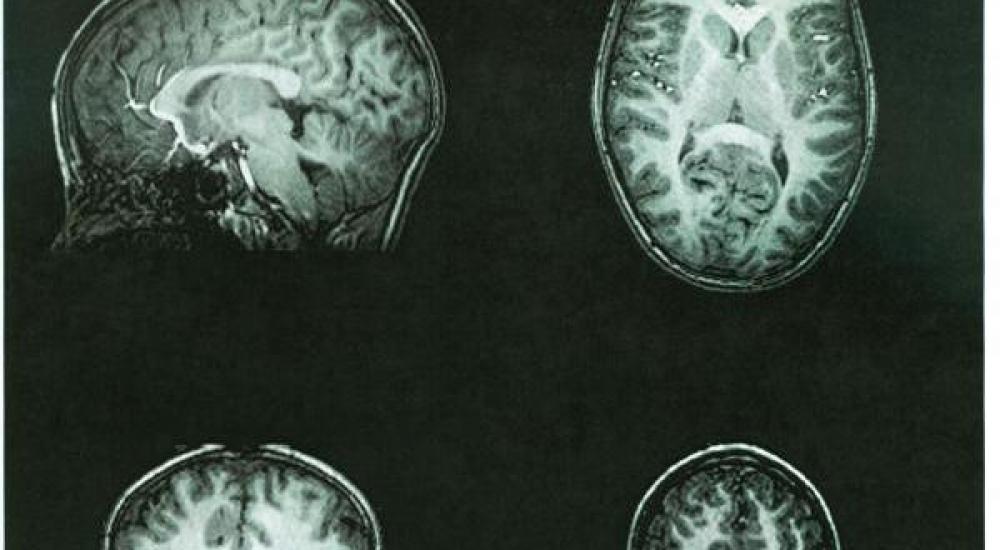

فقد أظهرت دراسة فرنسية أن الدماغ يتأثر بشكل مباشر ويكرس المزيد من الجهد للمؤشرات التي تدل على وجود تهديد.

ولأول مرة توصل الباحثون إلى أن مناطق معينة من الدماغ توجد بها أعصاب مسؤولة عما يسمى الحاسة السادسة تترقب وقوع مكروه وترصده قبل حدوثة بـ 200 جزء من الثانية.

كما لاحظ القائمون على هذه الدراسة بأن الأشخاص شديدي التوتر تختلف لديهم مناطق رصد المخاطر عن نظرائهم ذوي الأعصاب الهادئة ويتجاوبون معها بطريقة مختلفة ومناطق أخرى في الدماغ عن طريق تحديد ماهية الخطر بعكس الفئة الأخرى التي تحدده عن طريق تعابير الوجه.